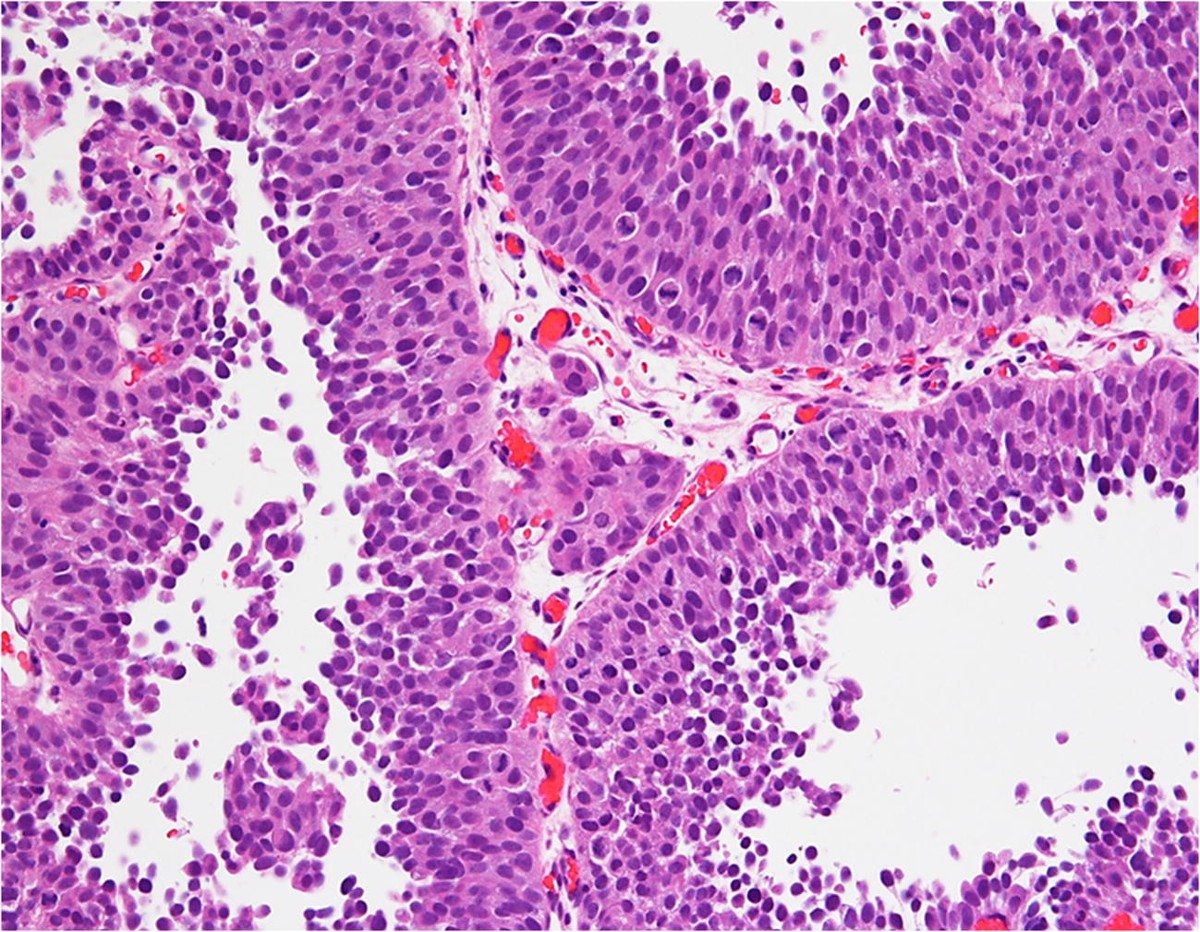

Mesane tümörleri, idrar kesesinin iç yüzeyini döşeyen ürotelyum adı verilen hücre tabakasından gelişir. Bu tümörler mikroskop altında incelendiğinde, hücrelerin derecesi (grade) belirlenir. Hücre derecesi, kanser hücrelerinin ne kadar anormal göründüğünü ve ne kadar hızlı büyüyebileceğini gösterir. İşte bu noktada “high grade” ifadesi devreye girer.

“High grade” Türkçeye “yüksek dereceli” olarak çevrilir. Bu, kanser hücrelerinin:

Normal hücrelere göre daha anormal göründüğü,

Daha hızlı büyüme ve yayılma eğiliminde olduğu,

Daha agresif davrandığı anlamına gelir.

High grade mesane tümörü, düşük dereceli (low grade) tümöre göre tekrar etme (rekürrens) ve ilerleme (progresyon) riski daha yüksek olan tümörlerdir.